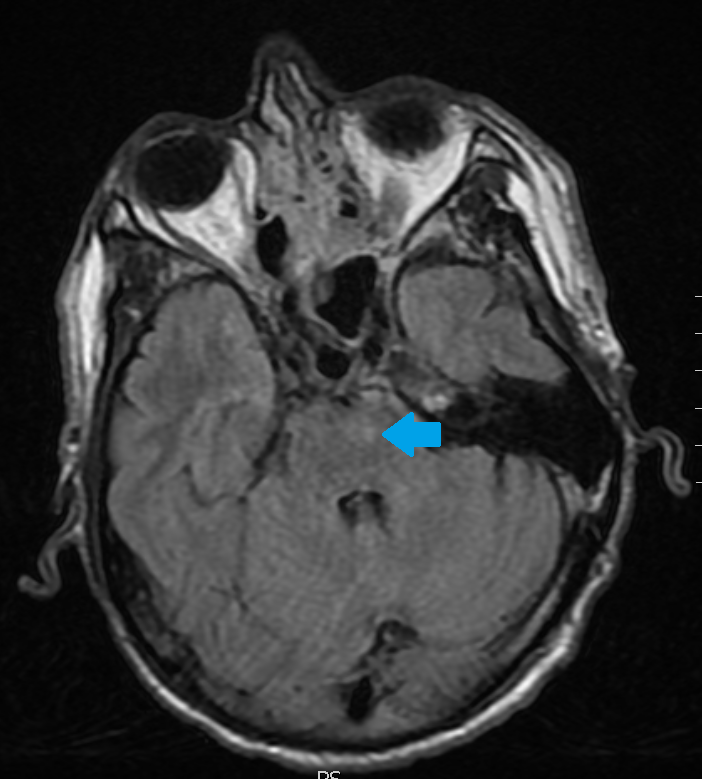

Scroll through the T2 FLAIR images in the slideshow below to follow a left basal ganglia injury with Wallerian degeneration of the descending motor axons in the brain stem.

The original injury was the small lesion on the first slide. The white matter abnormality pointed out on the subsequent slides is from Wallerian axonal degeneration.